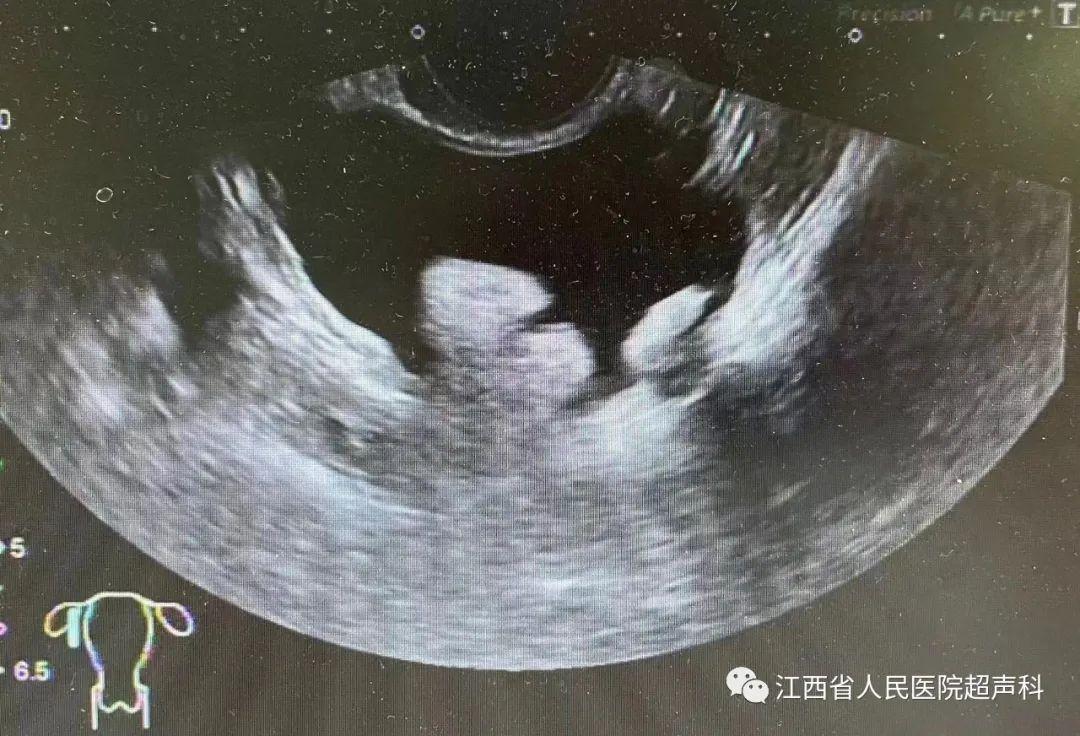

超声显示卵巢囊肿内含密集点状回声伴实性强回声成分时,多为卵巢畸胎瘤,超声诊断的敏感度为58%,特异度为99%。

超声提示囊肿为囊实性或内壁有乳头样突起时,恶性风险增至10%。